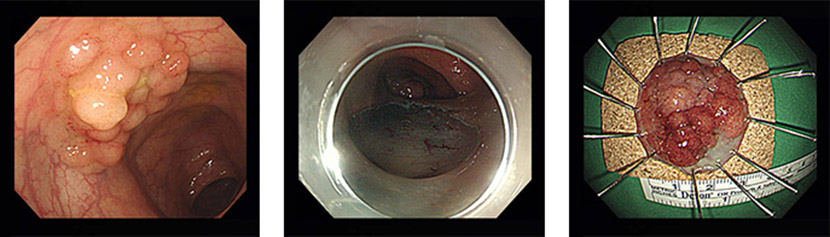

3. 结肠、直肠

1) 不局限于黏膜的5cm以下的分化型早期癌

2) 2cm以上的侧方发育型肿瘤(生长侧方向的肿瘤)

3) 2cm以上的无硬性息肉(不存在细小的喉咙的息肉)